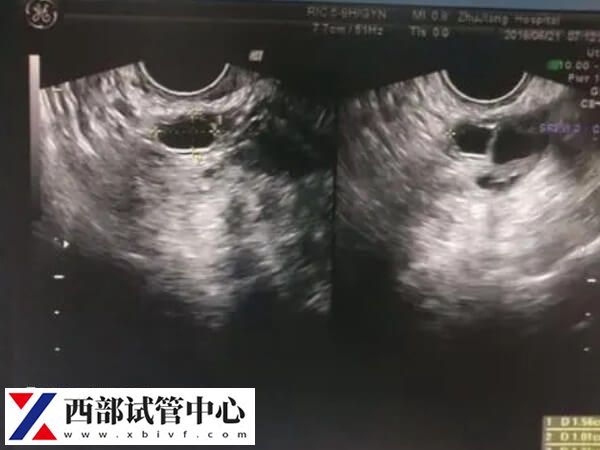

3、确定卵泡数量和质量

可测出卵巢中优质卵泡量,还能测出哪个卵巢排卵,以及卵泡质量如何,以及子宫内膜是否适合孕卵着床等。